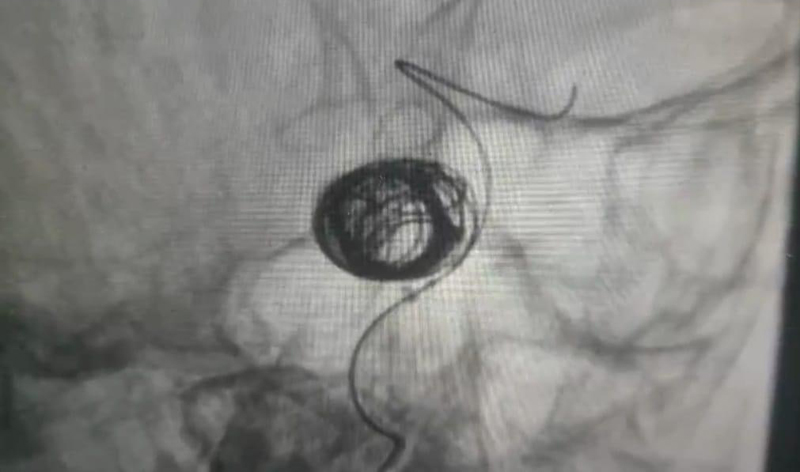

Hình ảnh can thiệp nội mạch thần kinh

Bệnh nhân K. được chỉ định chụp CT dựng hình mạch máu não (CTA) kết quả: Hình ảnh túi phình kích thước lớn động mạch cảnh (ĐMC) trong đoạn xoang hang trái. Bệnh nhân được chỉ định chụp mạch máu não số hóa xóa nền, với kết quả: Túi phình ĐMC đoạn xoang hang kích thước 4.6 x 3.4 mm, bờ nham nhở có nhú;Túi phình ĐMC cảnh đoạn xoang hang kích thước 15 x 13 x 4.6mm, bờ tròn đều. Sau khi hội chẩn với chuyên gia can thiệp nội mạch thần kinh của BV Đại học Y dược (ĐHYD) TP. Hồ Chí Minh, cân nhắc các yếu tố về kích thước, vị trí, hình thái học của túi phình. Ê-kip đã quyết định điều trị túi phình lớn bên trái bằng phương pháp can thiệp nội mạch gồm: stent chuyển dòng và coilling một phần túi phình nhằm ngăn ngừa túi phình vỡ. Chiều ngày 5/5/2022, các phẫu thuật viên (PTV) khoa Ngoại Thần kinh - BVĐK tỉnh Khánh Hòa phối hợp cùng PTV chuyên gia BV ĐHYD TP.HCM, tiến hành can thiệp nội mạch đặt stent chuyển dòng và coilling một phần túi phình. Sau 120 phút ca phẫu thuật kết thúc, bệnh nhân tỉnh táo, glassgow 15 điểm, dấu hiệu sinh tồn ổn định, không yếu liệt tứ chi và được theo dõi tại viện 3 ngày.